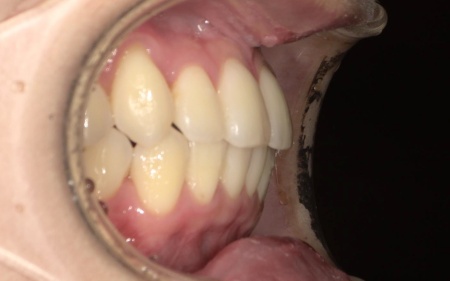

20代女性 八重歯と歯並びの乱れをマウスピース矯正装置で改善した症例

「上下の八重歯が気になる」とご相談いただきました。

拝見したところ、歯が正しく並ぶためのスペースが不足しており、歯が重なって生えてしまう叢生(そうせい)の状態が全体的に見られました。

特に上下の糸切り歯が外側にずれている、いわゆる八重歯が目立っています。

患者様の場合は上下あごの位置関係から噛み合わせに大きな問題はなく、横顔のバランスや鼻先とあごを結んだEラインにも目立った乱れは見られませんでした。